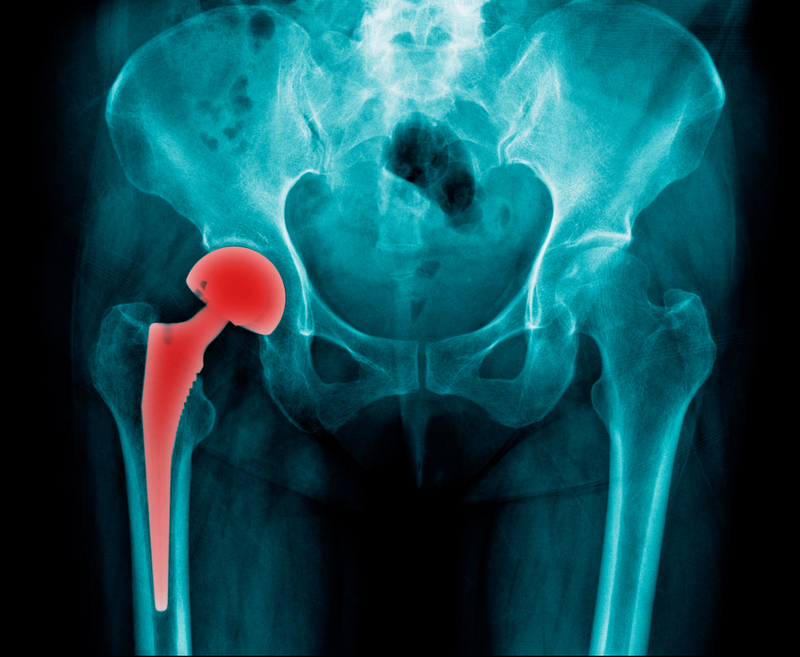

The matter came before the Central Information Commission after Mukesh Jain of Mumbai-based Manav Foundation had filed an RTI application seeking documents submitted by DePuy Medical Private Limited Ltd seeking clearance for import of medical devices "ASR XL Acetabular System" and "DePuy ASR Hip Resurfacing system" manufactured by DePuy International Ltd.

Jain challenged the contention of the CDSCO saying the matter pertains to large number of patients who had to suffer because of faulty products which were recalled by the United States. On being tested and found defective these implants have been banned from usage worldwide, but patients, mostly senior citizens in India, are being freely recommended and implanted with these allegedly cancer causing devices with far reaching complications, Information Commissioner noted in the order citing Jain's submissions.

Jain has clarified that the imported drug has been detrimentally affecting the senior citizens who have been administered such implants, he noted. The documents are required for proving the liability and onus of the companies in the case artificial hip implants imported by DePuy, Azad said.